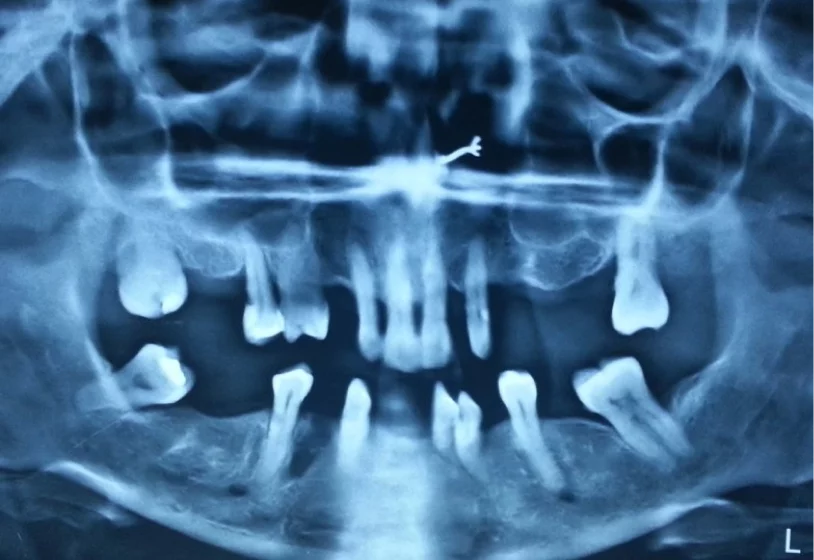

With over 20 years of expertise and over 30,000 successful implant placements, patients worldwide have embraced the transformative results.

Patients who were previously rejected for dental implant treatment elsewhere have successfully undergone the procedure with Dr. Vivek Gaur. All cases were completed within 48 hours!